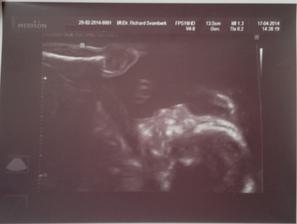

Jáchymek - -9. až 0. měsíc 🙂 - 2. těhotenství

24. srpna 2014 - 39+2tt - ve 4:24 hod. s mírami 49 cm a 2,97 kg se nám po náročném (pupečník kolem krku), ale zato rychlém porodu narodil náš druhý poklad. Šimonek mu vybral jméno Jáchym, my s tatínkem doplnili druhé jméno Pavel - JÁCHYM PAVEL KOLAŘÍK.